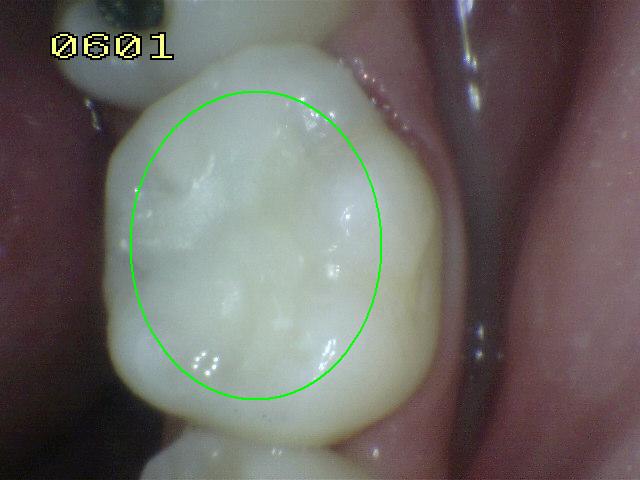

Código 2

(Caries Inicial): Lesión de

caries observada en esmalte en estado húmedo y permanece después de

secar.

- Si el margen de la

restauración está en esmalte, se debe observar el

diente húmedo. Cuando esta húmedo hay una opacidad

compatible con la desmineralización o pigmentación

que no corresponde a la aparencia clínica del

esmalte sano (Nota: la lesión sigue siendo visible

cuando se seca).

- Si el margen de restauración está en dentina: el

Código 2 corresponde a la pigmentación que no es

compatible con la aparencia clínica de la dentina o

el cemento sano.

- (Mancha blanca

/ marrón)